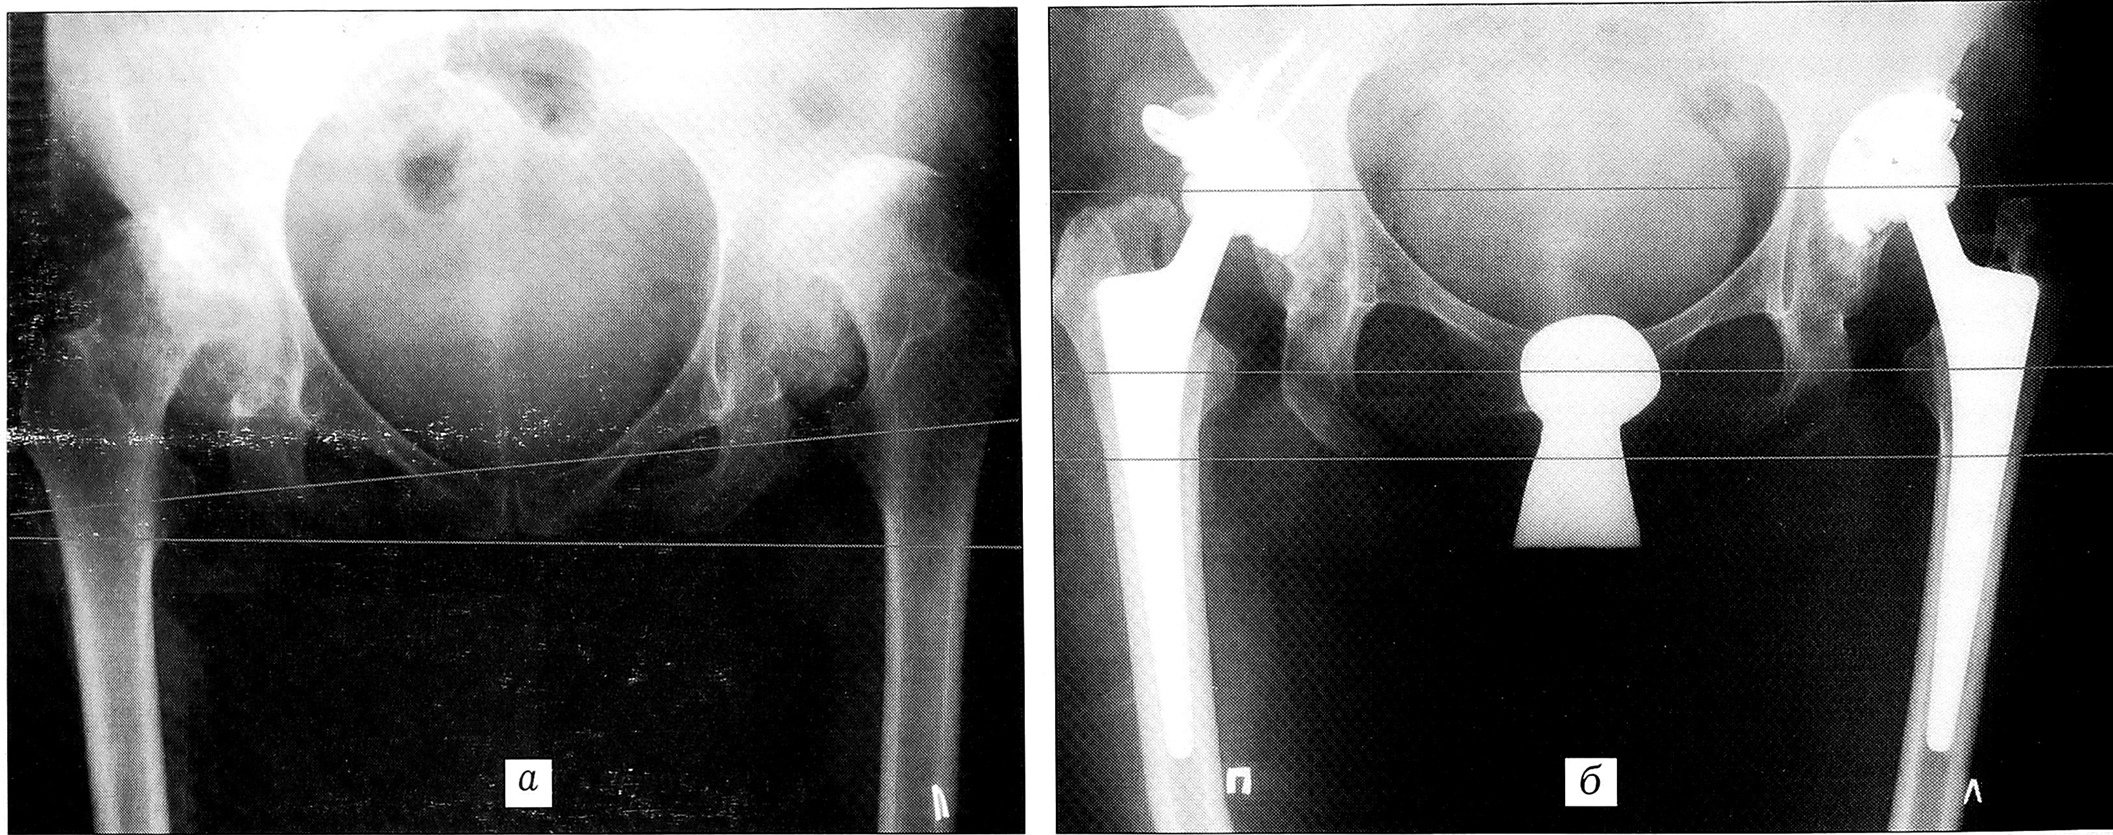

Рис. 1. Рентгенограммы больной Г. 47 лет. Диагноз: двусторонний диспластический коксартроз III стадии, сгибательно-приводящая контрактура обоих бедер, абсолютное укорочение левой нижней конечности на 3 см.а — до операции; б — через 9 лет после операции на правом и 9,5 лет — на левом тазобедренном суставе: восстановлены длина и функция конечности, хорошая остеоинтеграция компонентов эндопротеза.

Больная Г., 47 лет. Диагноз: двусторонний диспластический коксартроз III стадии, сгибательно-приводящая контрактура обоих бедер, абсолютное укорочение левой нижней конечности на 3 см (рис. 1, а). Произведено эндопротезирование обоих тазобедренных суставов с интервалом в 5 мес. Слева: бесцементная система Споторно; справа: ацетабулярный компонент — оригинальная чашка Мюллера на винтах с пластикой крыши вертлужной впадины аутотрансплантатами из резецированной головки бедренной кости; бедренный компонент — бесцементная ножка Споторно. Восстановлены длина и функция нижних конечностей. Срок наблюдения 9 лет после операции на правом и 9,5 лет — на левом суставе (рис. 1, б): продолжает работать по специальности (врач).